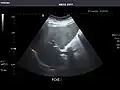

Aorta: Visualized portions normal in caliber, 16 x 15 mm.

Aorta -